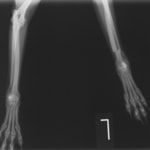

症例3:キルシュナーワイヤーのピンニングによる整復

ペルシャ猫 11ヶ月齢 雄

他院にて左大腿骨遠位の成長板骨折(salter-harrisⅠ型)が認められており、治療相談を目的として来院。当院にて、キルシュナーワイヤーを用いたピンニングにより骨折部位の整復を行いました。術後の経過は良好で、現在も経過観察中です。

術前レントゲン

術後レントゲン